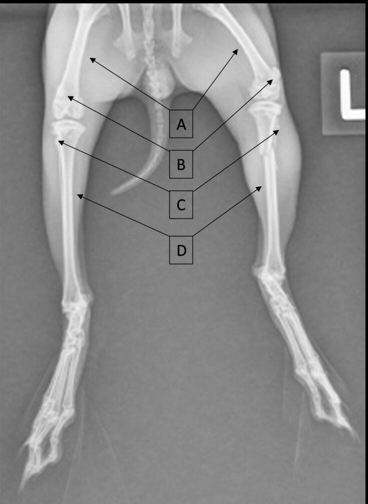

Identify the labeled structures

A

A = femur

B = patella

C = fibula

D = tibia